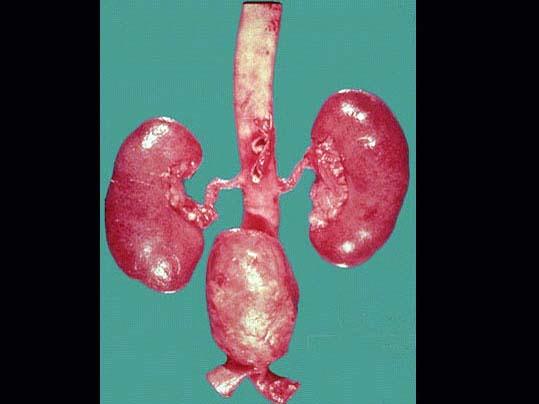

问题 动脉粥样硬化患者腹主动脉出现一巨大肿物,巨检如图所示,镜下见瘤壁由萎缩的动脉内、中、外膜构成,该病变最确切的名称是 ( )

选项 A.血肿 B.假性动脉瘤 C.真性动脉瘤 D.夹层动脉瘤 E.以上均不是

答案 C